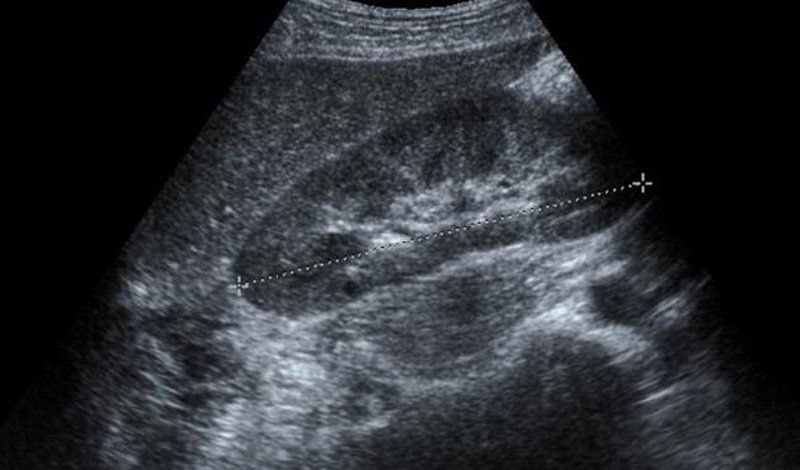

Hiện nay, siêu âm gan là phương pháp chẩn đoán hình ảnh hiện đại, cho phép thấy rõ cấu trúc gan bao gồm các thùy gan, phân thùy và các hạ phân thùy gan, cũng như hệ thống cấu trúc mạch máu của gan bao gồm động mạch chủ gan, tĩnh mạch chủ dưới gan, tĩnh mạch cửa gan và tĩnh mạch trên gan.

Qua đó, siêu âm gan giúp phát hiện những tổn thương ở gan, bao gồm các bệnh lý ở gan như xơ gan, ung thư gan, ... đánh giá mức độ gan nhiễm mỡ. Kết quả siêu âm gan là cơ sở quan trọng dùng trong chẩn đoán và định hướng điều trị những thương tổn gan.

Kết quả siêu âm gan bình thường phải cho thấy những đặc điểm về các cấu trúc đường viền, nhu mô và mạch máu trong nhu mô gan như sau:

2.3 Cấu trúc mạch máu trong nhu mô gan

- Hệ tĩnh mạch cửa gan có cấu trúc hình ống, rỗng âm, thành nét đậm. Từ rốn, hệ tĩnh mạch cửa chạy vào các thùy gan và hạ phân thùy gan.

- Cấu trúc tĩnh mạch gan là cấu trúc ống, lòng ống rỗng âm, thành ống không có đường viền, khi thở, đường kính của tĩnh mạch thay đổi, đường kính vùng hợp lưu < 1cm.

- Trên hình ảnh siêu âm gan, động mạch gan và các nhánh động mạch gan ít được nhìn thấy khi phân chia theo hệ tĩnh mạch cửa gan.